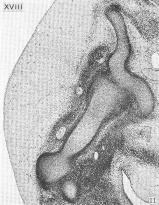

Carnegie Stage 18 Figures

Transverse section of definitive thyroid gland

Transverse section of median thyroid